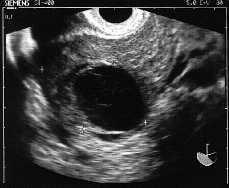

Figura 1. Imagen ecográfica de OI.

-- OI de 58 * 36 mm con imagen redondeada econegativa de 30 mm de diámetro con algún eco en su interior.

-- Diagnóstico compatible con EE en trompa derecha no accidentado en el momento del diagnóstico y OI quístico.

El hallazgo de un EA en estadio precoz (5,5 semanas) ha sido en este caso un hecho fortuito, ya que el diagnóstico temprano de un EA es difícil, pero esencial, dado que la separación de la placenta puede asociarse con una hemorragia fatal(8,9). Por otro lado, la ecografía al principio suele confundir el EA con uno tubárico, como es nuestro caso, pero a medida que evoluciona la gestación se hace más fácil el diagnóstico(10,11).